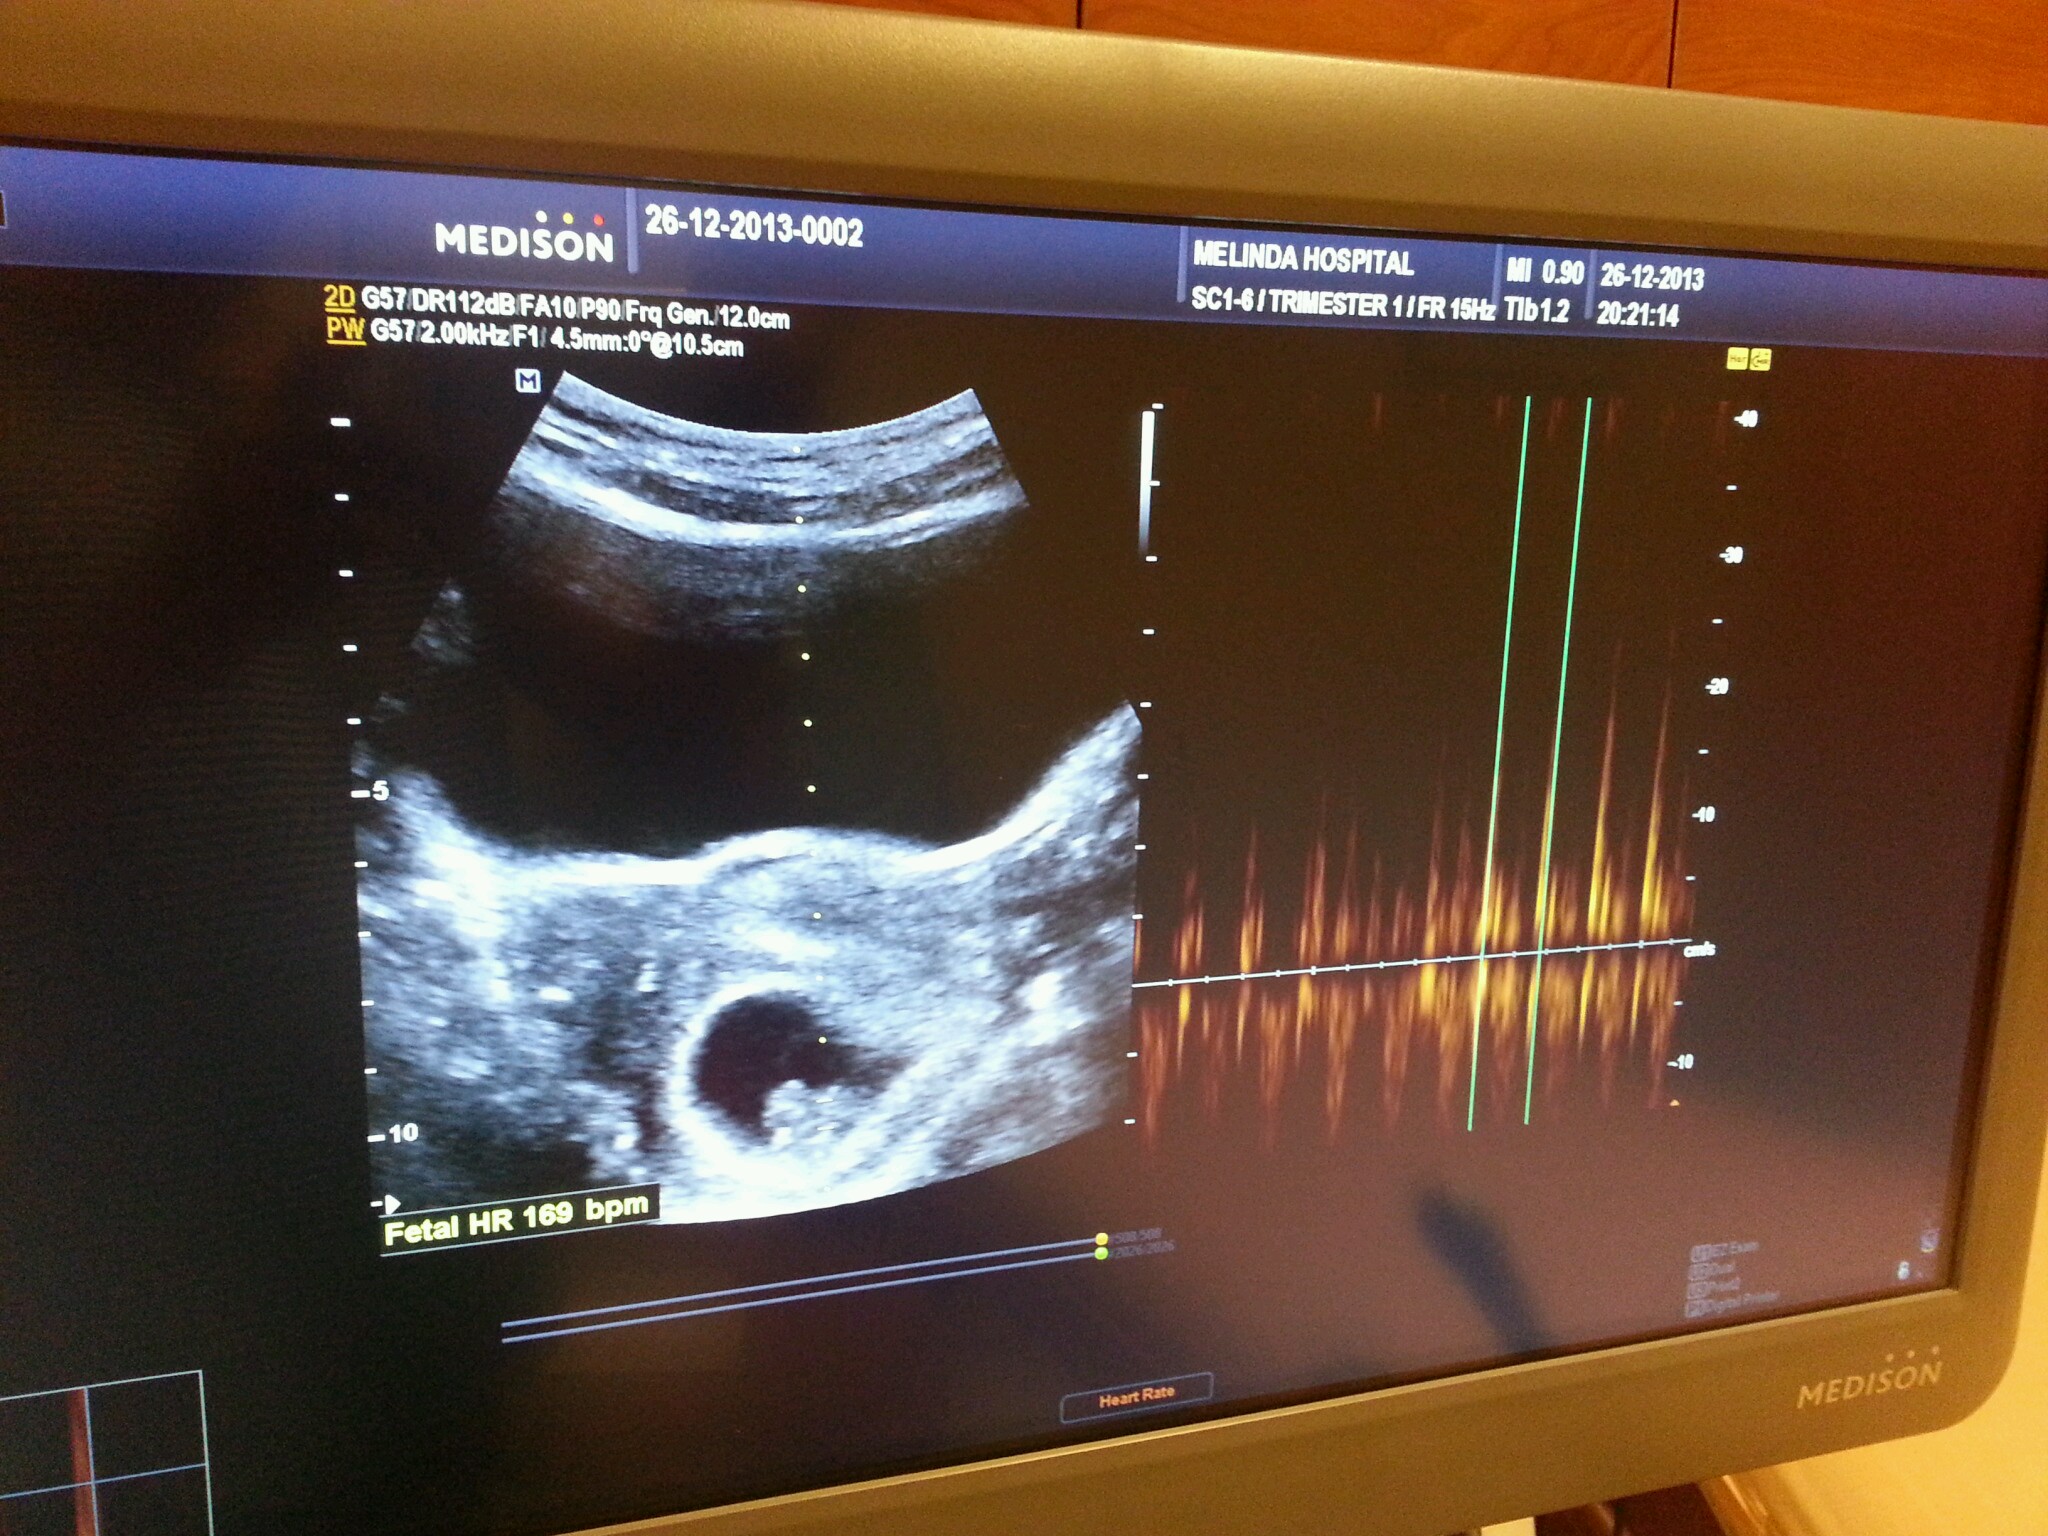

usg at 8 weeks

We heard your heartbeat for the first time. We’re madly in love with you now… your heartbeat was 169 per minute. You must be so excited growing and developing that your heart beats that fast! Daddy was so delighted to know that you’re well.

your heartbeat was 169 per minute